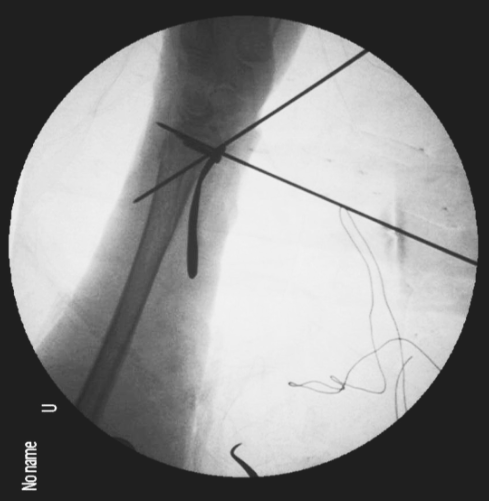

经皮克氏针固定:

克氏针固定治疗桡骨远端骨折是一种经典的治疗方法。经皮克氏针固定符合骨折的微创治疗原则,并且可灵活应用于骨折的复位。但是克氏针固定也存在相对的禁忌证,主要是严重的骨质疏松骨折和严重粉碎的关节内骨折。此外,克氏针固定还可以作为外固定或者钢板固定的辅助治疗。